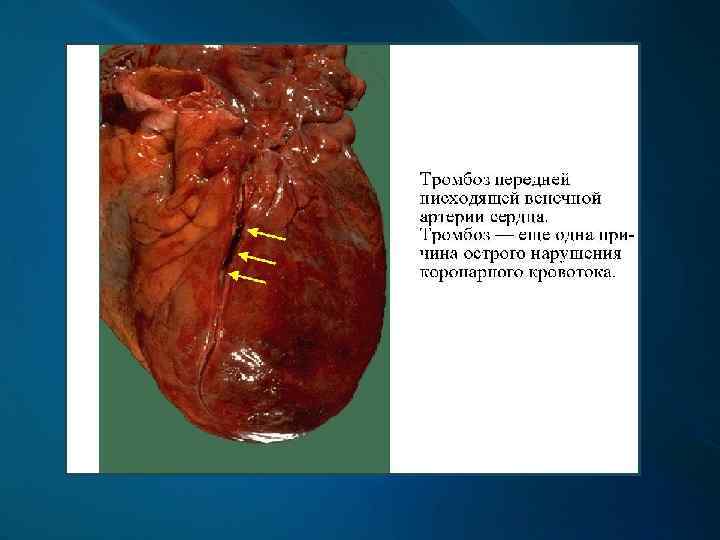

Клинические проявления и осложнения Атеросклероз венечных артерий сердца проявляется их стенозом, вызывающим приступы стенокардии, осложняется развитием инфаркта миокарда.

Инфаркт миокарда - очаг некроза, возникший вследствие острого несоответствия между потребностью миокарда в кислороде и доставкой его по коронарным артериям. Зона некроза при инфаркте пространственно увязана с бассейном конкретной артерии.